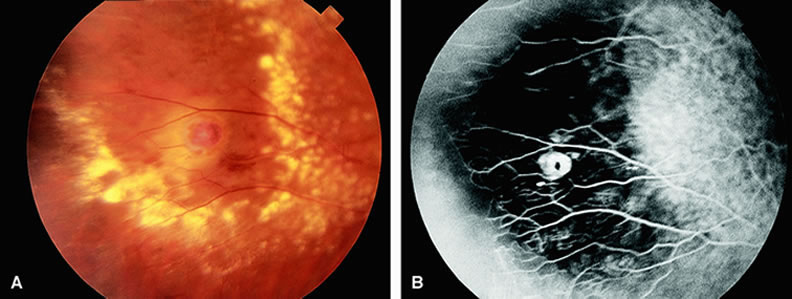

Normally, the choriocapillaris is completely filled with fluorescein dye within 5 seconds after the first appearance of dye within it. In eyes with the ocular ischemic syndrome, this filling can be delayed in extreme cases for 1 minute or longer. The posterior choroid is supplied by the temporal and nasal posterior ciliary arteries.2 In some normal eyes, but particularly in eyes with the ocular ischemic syndrome, delayed, asymmetric filling of the areas supplied by these vessels can be seen (Fig. 1). Filling of the retinal arteries is often also delayed in eyes with the ocular ischemic syndrome, and this manifests as a delayed arm-to-retina circulation time. Although the retinal arteries usually start to fill within 15 seconds after an antecubital intravenous injection of sodium fluorescein dye, this time range varies according to several factors, including the site of injection, the rate of injection, and body circulation. A visible leading edge of dye (see Fig. 1) within a retinal artery is almost always abnormal after an intravenous injection and indicates diminished flow. In the Retina Vascular Unit at Wills Eye Hospital, Philadelphia, the upper-normal limit for retinal arteriovenous transit time (time from the first appearance of dye in the temporal retinal arteries of the arcades to the time when the corresponding veins are completely filled) is considered to be 10 to 11 seconds. The retinal arteriovenous transit time is usually prolonged in eyes with the ocular ischemic syndrome; in fact, this prolongation of time is the most common fluorescein angiographic feature in eyes with the ocular ischemic syndrome. Leakage of fluorescein dye from the retinal vessels, particularly the arteries, occurs in 85% of eyes with the ocular ischemic syndrome (Fig. 2). Presumably, hypoxia and subsequent endothelial cell damage cause this leakage of dye. Leakage of fluorescein dye from the retinal vessels can be seen in the posterior pole and periphery. This hyperpermeability, combined with leakage of serum from microaneurysmal abnormalities, appears to account for the macular edema observed in some eyes with the ocular ischemic syndrome (see Fig. 2). Leakage of fluorescein dye from neovascularization of the disc is seen in approximately one third of eyes with the ocular ischemic syndrome (see Fig. 2). Hyperfluorescence resulting from leaking neovascularization of the retina is less common. Retinal capillary nonperfusion is visible on fluorescein angiography in some cases. Ischemic optic neuropathy is rarely observed. Iris neovascularization is found in approximately two thirds of cases at the time the diagnosis is made. Fluorescein angiography is helpful in differentiating the ocular ischemic syndrome from conditions that can mimic it, including central retinal artery obstruction, mild central retinal vein obstruction, and diabetic retinopathy. Of these conditions, only the ocular ischemic syndrome has delayed choroidal filling present. Moreover, late staining of the retinal arteries is unusual with the other conditions. An increased arteriovenous transit time is usually present in eyes with the ocular ischemic syndrome but can also be seen in eyes with central retinal artery or vein obstruction and eyes with diabetic retinopathy and nonperfusion of the retinal capillary bed. OPHTHALMIC ARTERY OBSTRUCTION Clinically, acute ophthalmic artery obstructions differ from acute central retinal artery obstructions in that persons with the former often have no light perception and the retinal whitening appears more intense on examination.3 A cherry-red spot is often absent in eyes with acute ophthalmic artery obstruction, but its presence does not rule out the diagnosis (Fig. 3A). Electroretinography often reveals diminished amplitudes of both b- and a-waves that are caused by inner and outer retinal ischemia, respectively.3 In contrast, with a central retinal artery obstruction alone, the a-wave amplitude is usually normal and the b-wave amplitude is often diminished because of inner retinal ischemia.4 Fluorescein angiography of eyes with acute ophthalmic artery obstruction shows delayed filling of the retinal vessels and usually the choroidal vessels as well (see Fig. 3B and C). Focal, pinpoint areas of staining resulting from leakage of dye at the level of the retinal pigment epithelium can be seen in some instances. Diffuse staining is also occasionally observed. Prominent staining of the retinal vessels is usually absent with acute ophthalmic artery obstruction, although it can be seen with chronic ophthalmic artery obstruction. RETINAL ARTERY OBSTRUCTION With acute central retinal artery obstruction, filling of the choroid is usually normal. Filling of the retinal arteries is often delayed, and in severe cases, a leading edge of dye can be seen (Fig. 4). A delay in retinal arteriovenous transit time is often noted.5 Box-carring or segmentation of the dye column can be seen in both the retinal arteries and veins when the obstruction is marked. In some cases, the flow appears normal because reperfusion of the blocked artery can occur fairly rapidly.6 Intraretinal leakage of dye in the late phases of the study, in a pattern consistent with macular edema, is generally not seen in eyes with acute central retinal artery obstruction. Fluorescein angiography can help identify eyes with acute central retinal artery obstruction in instances when the retinal whitening is subtle and the diagnosis is in question. Approximately 10% of eyes with acute central retinal artery obstruction have a cilioretinal artery that supplies the retina in the papillomacular bundle and extends into the foveola.7 In more than 80% of these eyes, the visual acuity eventually improves to 20/50 or better. Fluorescein angiography typically shows earlier filling within the patent cilioretinal artery and the veins draining the area that it supplies compared with the filling of the remainder of the retina, which is supplied by the central retinal artery (Figs. 5 and 6). Fluorescein angiography of eyes with marked, acute branch retinal artery obstruction reveals a lack of filling of the retinal capillary bed within the distribution of the involved vessel. Retinal veins that normally drain the damaged area also demonstrate a delay in filling. With severe blockage, retrograde filling can be seen in the distal aspect of an obstructed branch retinal artery (Fig. 7). Cilioretinal artery obstruction is similar to branch retinal artery obstruction except that the former vessel usually emanates from the edge of the optic disc (Fig. 8). Cilioretinal artery obstructions can be seen as isolated fundus abnormalities or in association with central retinal vein obstruction or acute anterior ischemic optic neuropathy.8 Cotton-wool spots are small areas of superficial retinal whitening that usually develop secondary to obstruction of axoplasmic flow caused by areas of focal retinal ischemia.9 Fluorescein angiography in these cases usually demonstrates relative hypofluorescence in the early and middle phase of the study (Fig. 9). Late staining of the cotton-wool spot can occur. As shown in Table 2, the differential diagnosis of cotton-wool spots is extensive; however, cotton-wool spots are most commonly observed in the setting of diabetic retinopathy, hypertensive retinopathy, collagen vascular disease, or hematologic abnormalities.